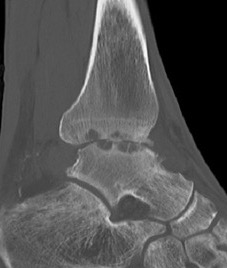

CT

Evaluate bone stock to determine if TAR is appropriate